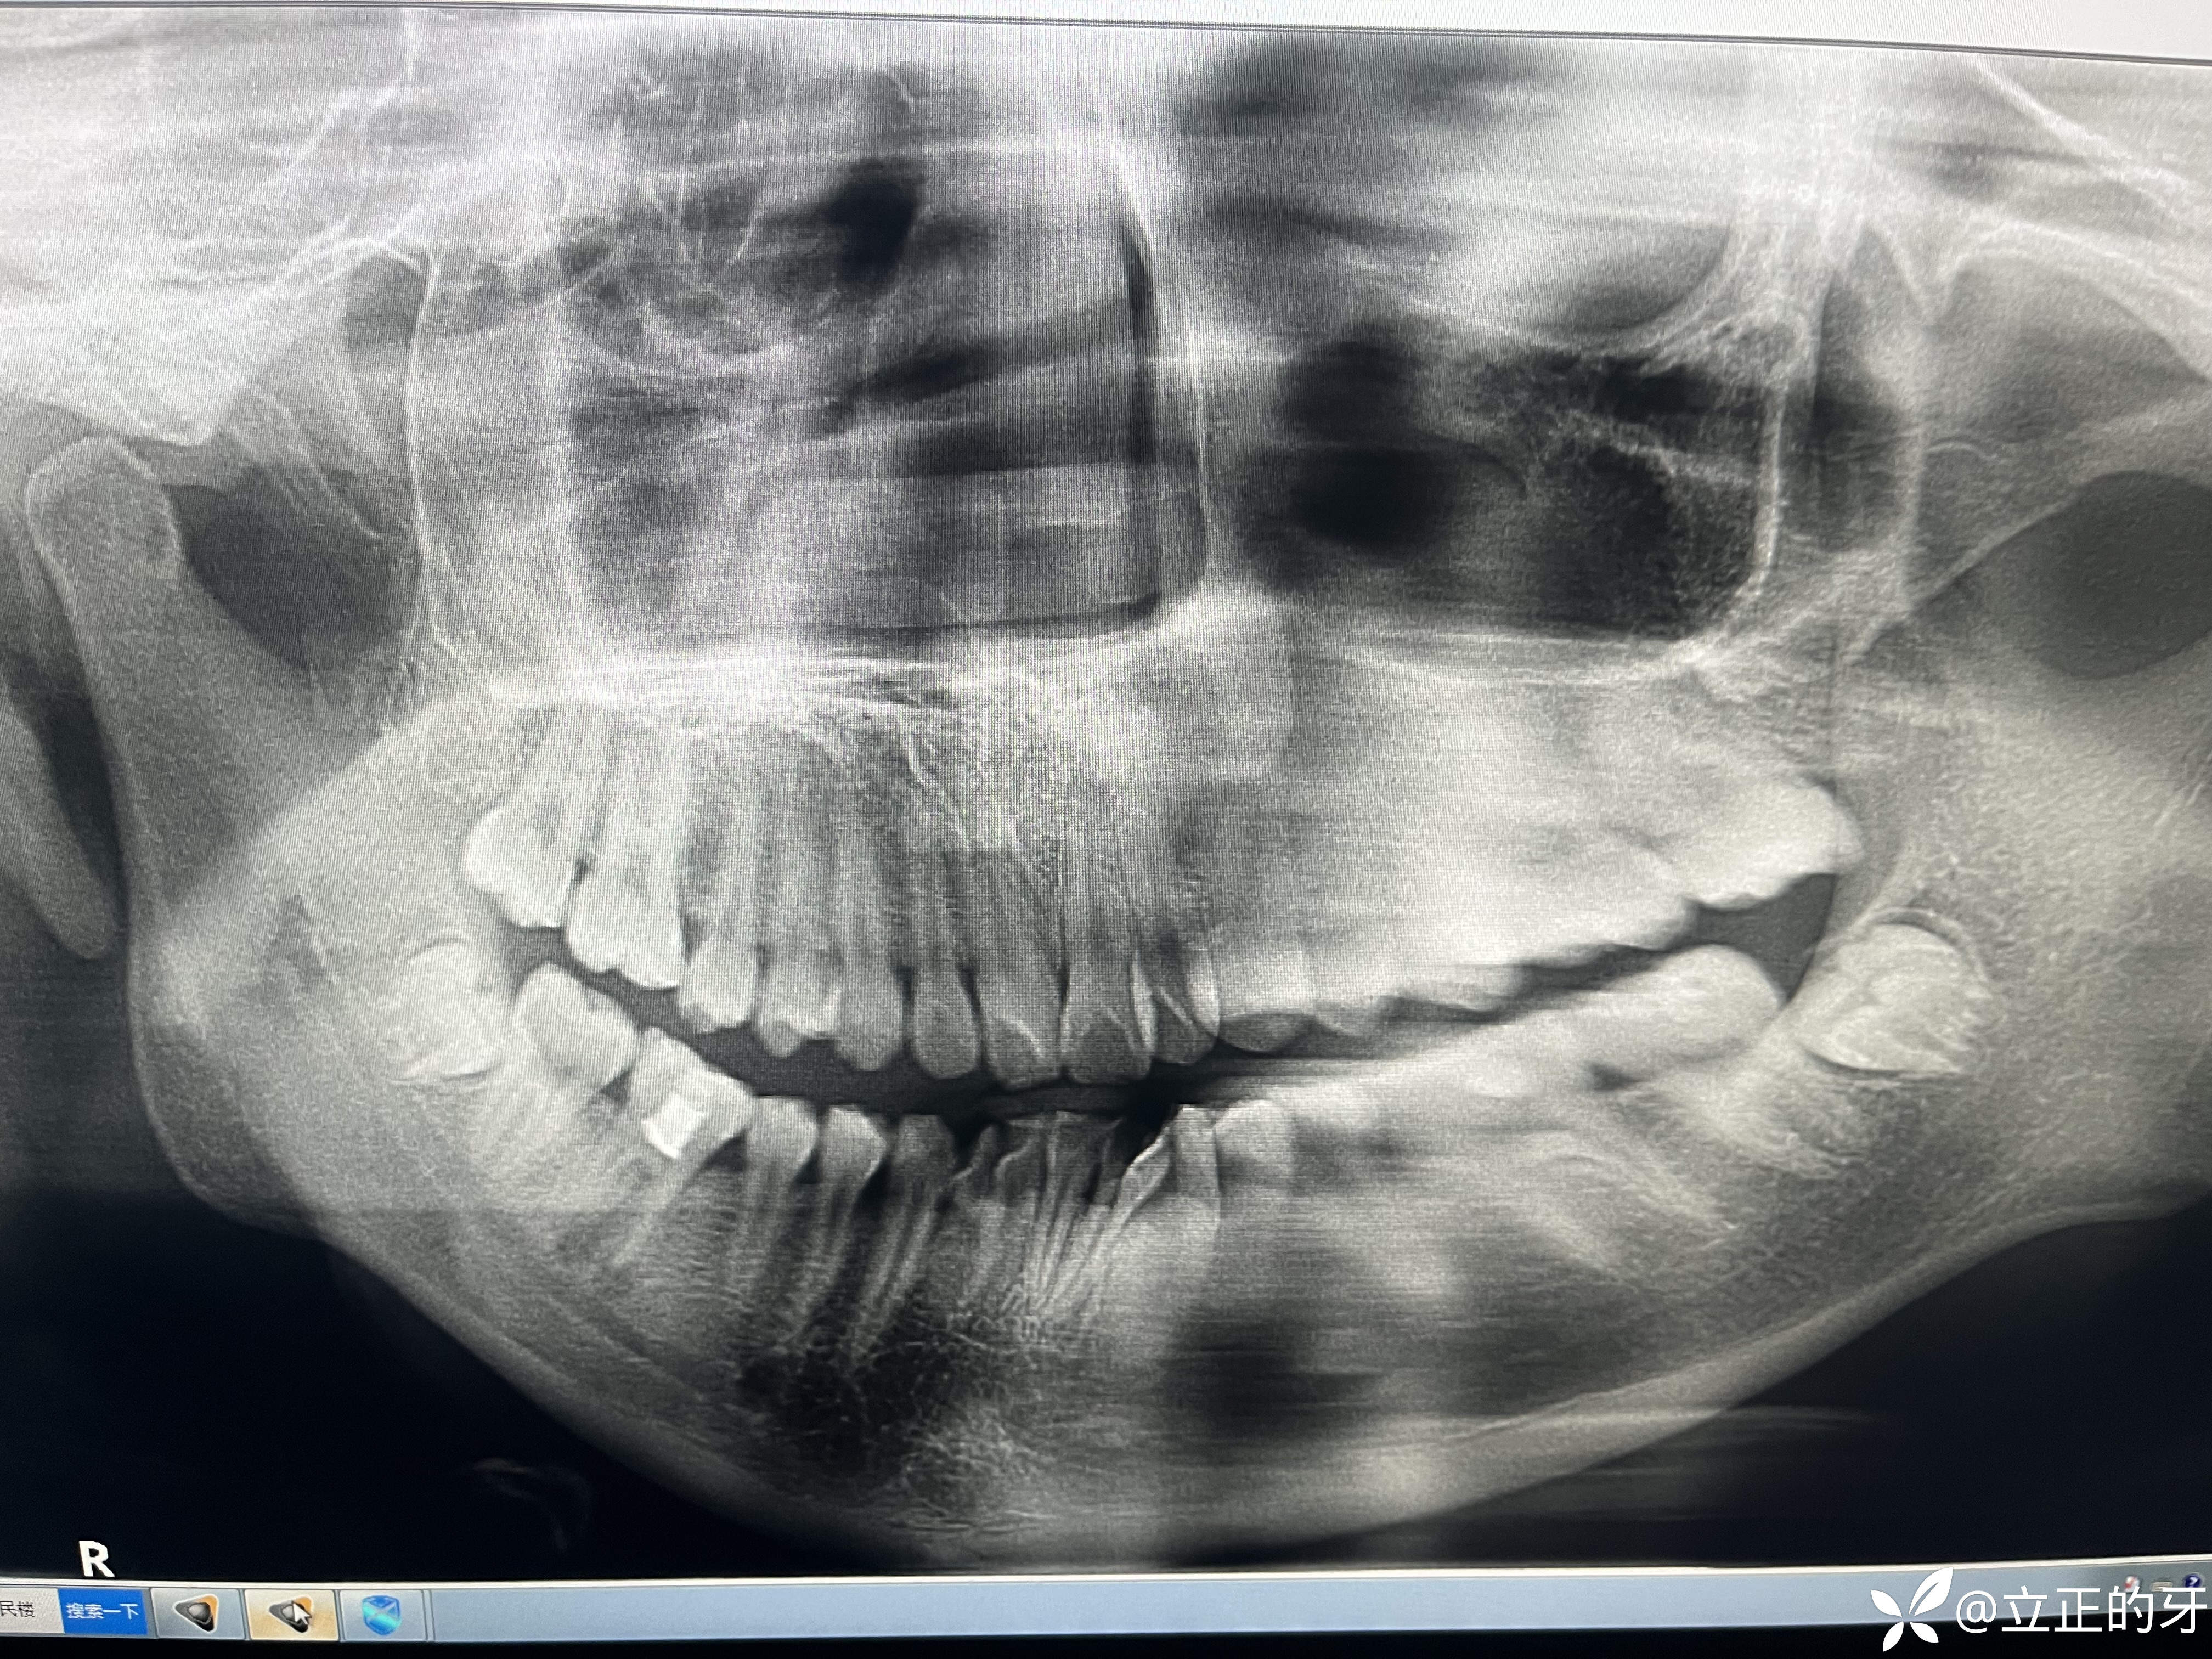

检查:37、47浅龋,46颊侧继发龋,45浅龋

那天曲面断层机器有点问题,左侧没拍好

原本想判断37、47龋坏情况,患者说第一磨牙做过治疗,拍片却发现46根管根本没有填充,且根尖处已经出现炎症!